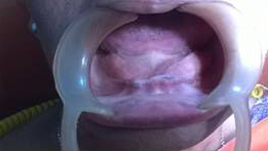

Before Placement of Prosthesis

Use of Bone Graft & GTR membrane for an Implant